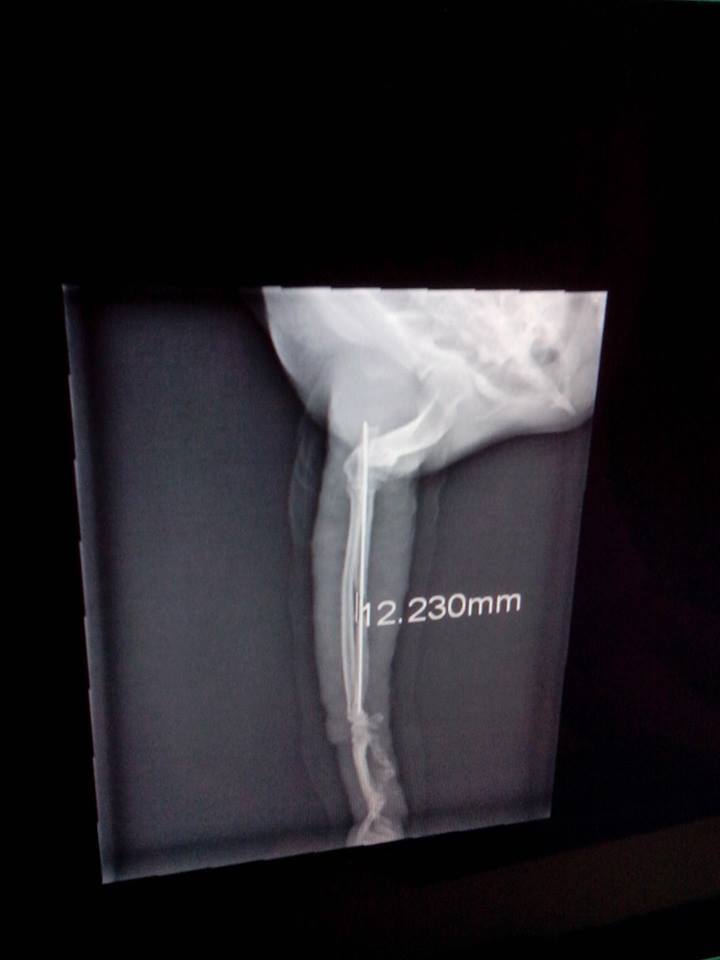

主題: 右前腳骨折的已結紮公貓-抓抓 申請者姓名: 程修芳 花色: 申請日期: 2013-11-02 08:36:06 申請者部落格: 申請者臉書網址: 所在縣市/合作醫院: 台南市/啄木鳥動物醫院 治療費用: 15970元 需求人數: 17人 已結案 (2014-01-10 18:02:14) 報名人員: ChiouYueh Shyu、Hui - Lan Zhuang(已付款)、ERic YU(已付款)、周小蕾(已付款)、WeiLin Chen(已付款)、WeiMin Lin(已付款)、Sky Lin(已付款)、謝小馬(已付款)、00(已付款)、Candace Shiue(已付款)、ginatw(已付款)、Helen Saroja Chen(已付款)、邱小祈(已付款)、nicole chen(已付款)、邱小祈、周星星(已付款)、周星星、Even Chen(已付款)、SASA(已付款)、小可(已付款)、 候補人員: 動物病情說明: 昨日發現自家附近已結紮公貓走路時右前腳一拐一拐的,因為抓抓很親人可以摸,所以大緻摸了一下發現有異樣, 經送啄木鳥醫院拍了X光, 發現右前腳有骨折現象, 需關籠休養,請問我可以申請醫助嗎? 動物近況說明: 經檢測2合一抓抓是愛滋猫, 所以即使固定了腳, 骨頭也沒有自動癒合, 所以必須要打鋼針固定, 目前已完成右前腳骨頭固定手術,已於 11/28日拆線, 在醫院休養.